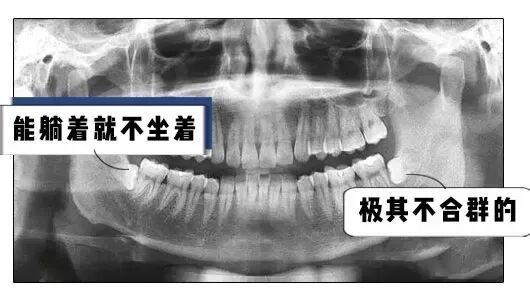

可是一般人的智齿都是这样长的

这样长的

甚至还有这样长的